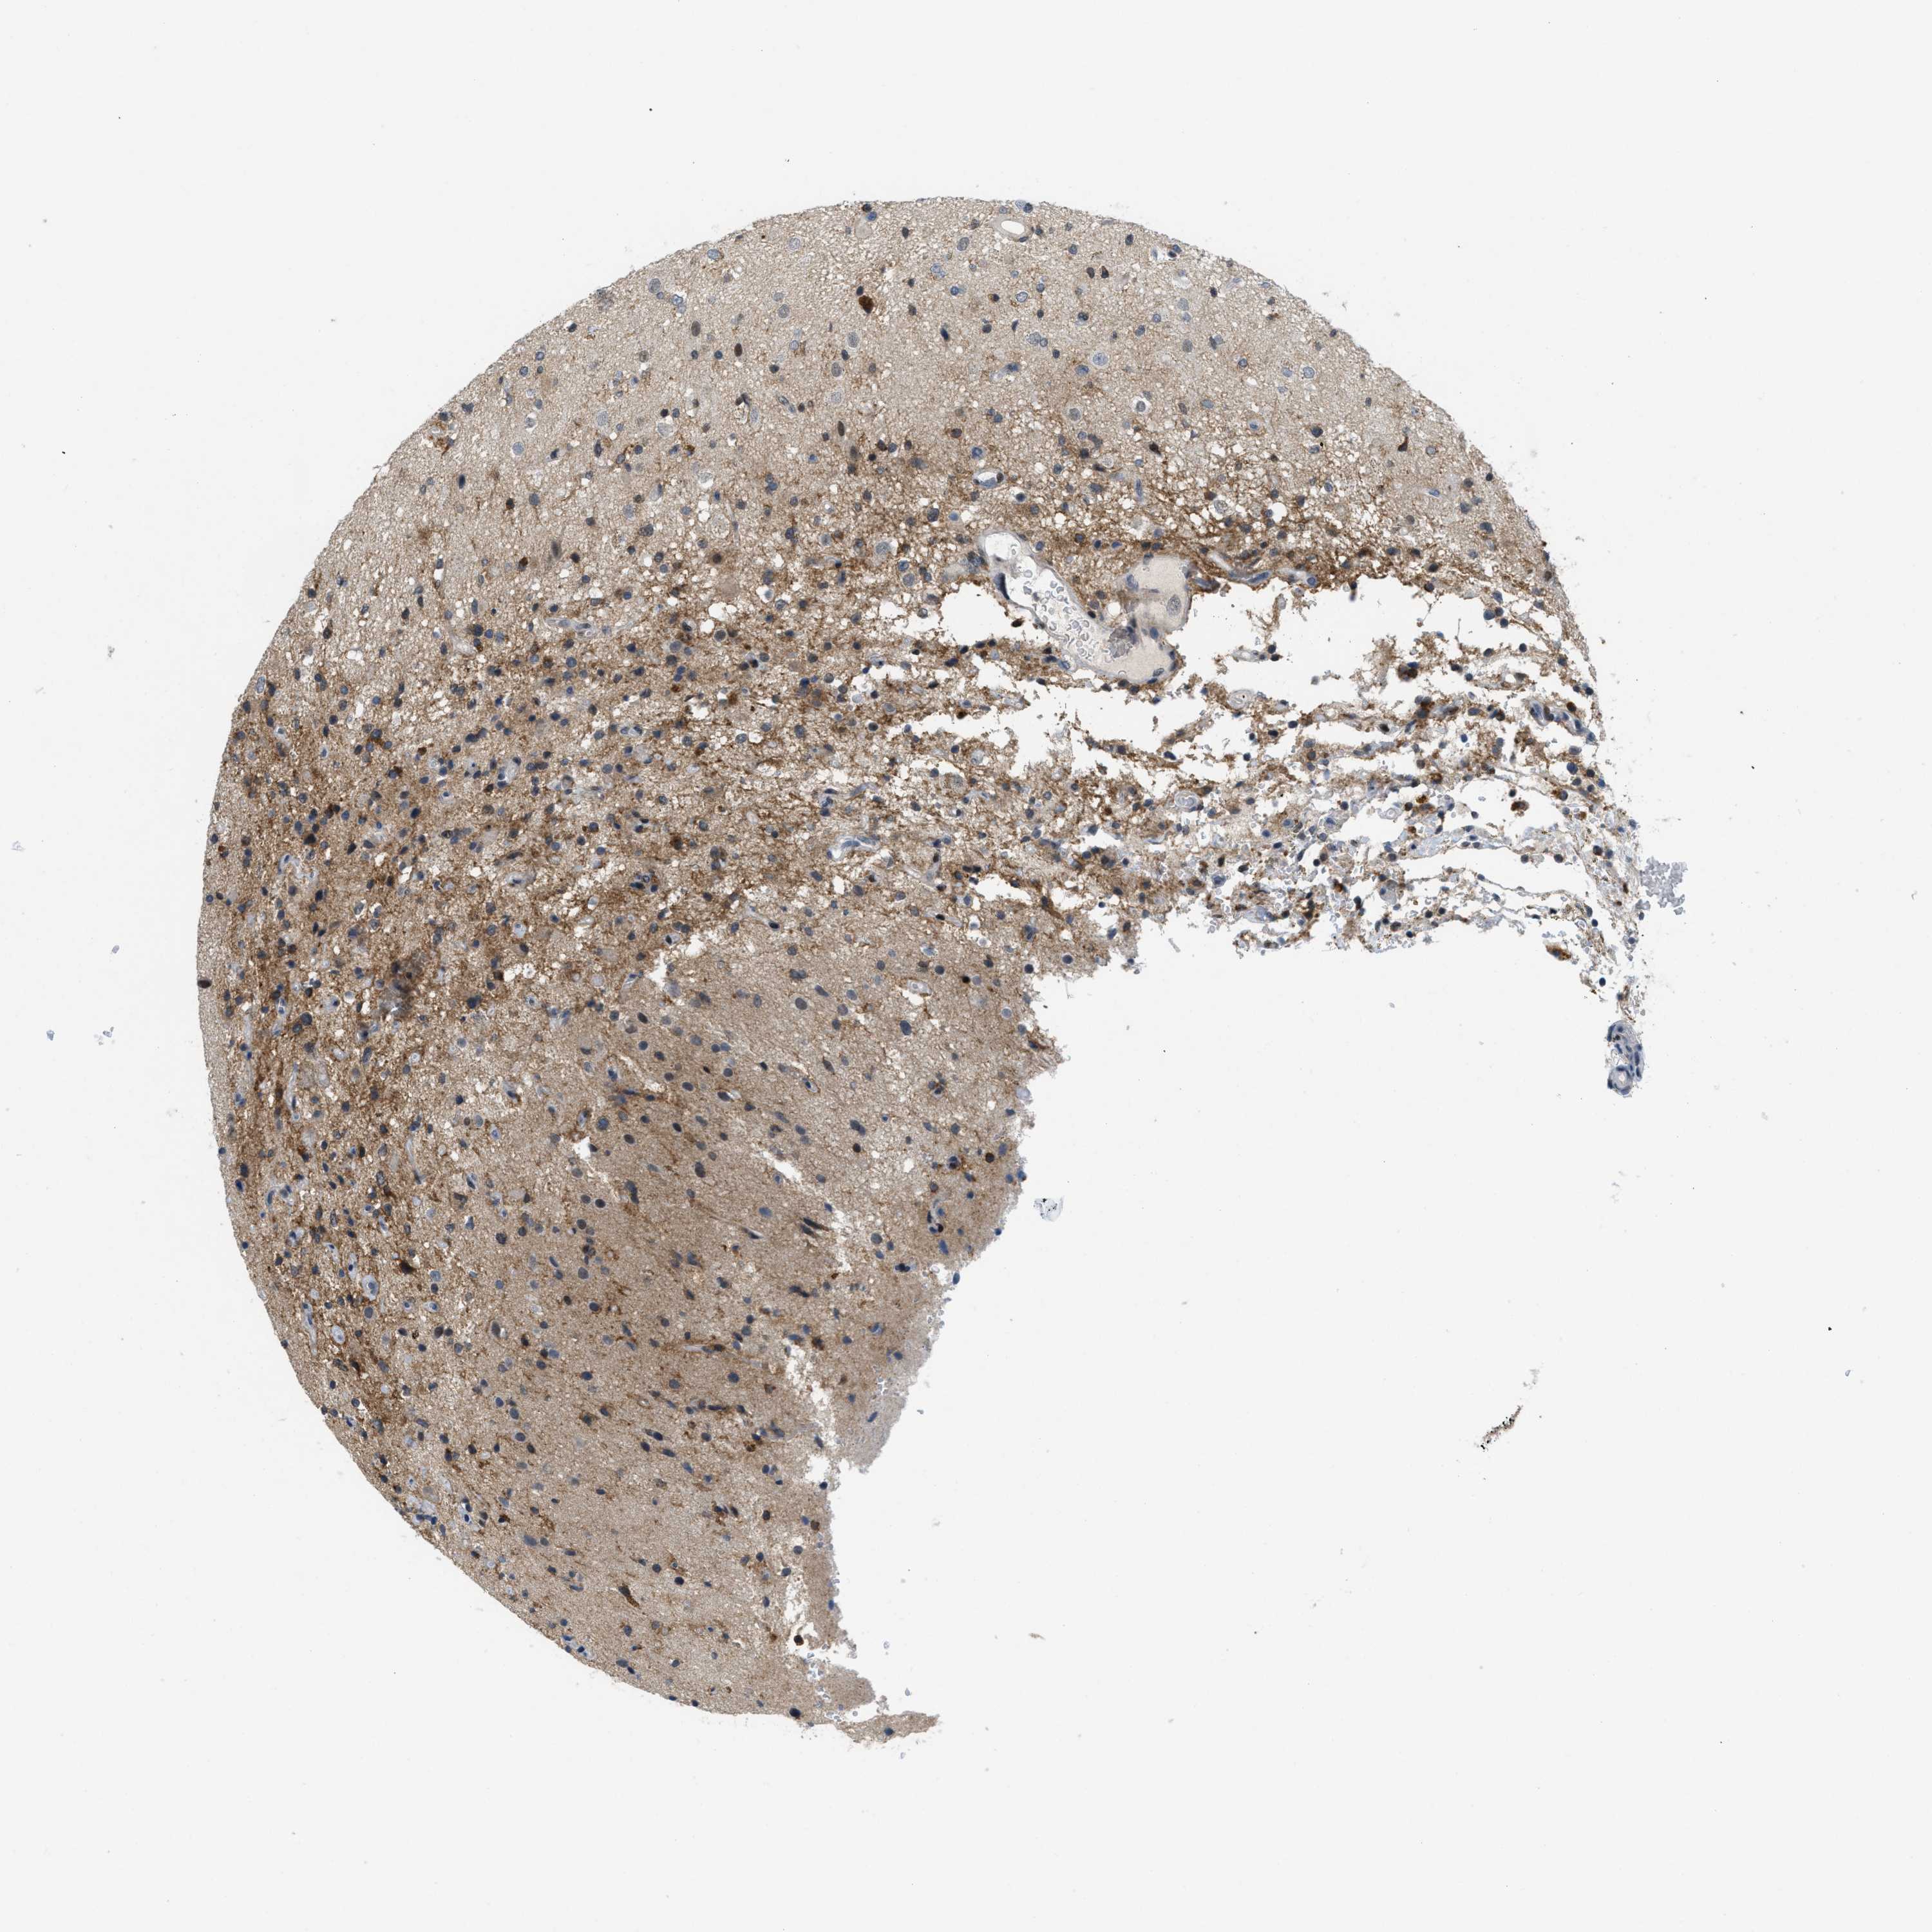

GLIOMA - Protein expressioni

A mouse-over function shows sample information and annotation data. Click on an image to view it in a full screen mode. Samples can be filtered based on level of antibody staining by selecting one or several of the following categories: high, medium, low and not detected. The assay and annotation is described here.

Note that samples used for immunohistochemistry by the Human Protein Atlas do not correspond to samples in the TCGA dataset.

Antibody stainingi

Antibody staining in the annotated cell types in the current human tissue is reported as not detected, low, medium, or high, based on conventional immunohistochemistry profiling in selected tissues. This score is based on the combination of the staining intensity and fraction of stained cells.

Each image is clickable and will lead to virtual microscopy that enables deeper exploration of all samples and also displays staining intensity scores, fraction scores and subcellular localization as well as patient and tissue information for each sample.

Antibody CAB016136

Antibody CAB017773

Staining

High

Medium

Low

Not detected

Intensity

Strong

Moderate

Weak

Negative

Quantity

>75%

75%-25%

<25%

None

Location

Nuclear

Cytoplasmic/membranous

Cytoplasmic/membranous,nuclear

Glioma, malignant, High grade

Glioma, malignant, Low grade